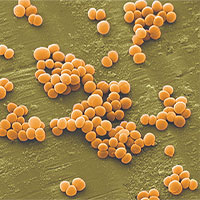

Vi khuẩn tụ cầu vàng xâm nhập qua thực phẩm nguy hiểm thế nào?